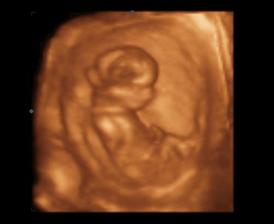

14.1.2010 3D ultrazvuk podľa PM presne 13tt+0 , na drobčeka sa bol pozrieť 1.krat aj tatinko, bolo to krásne 🙂 /////